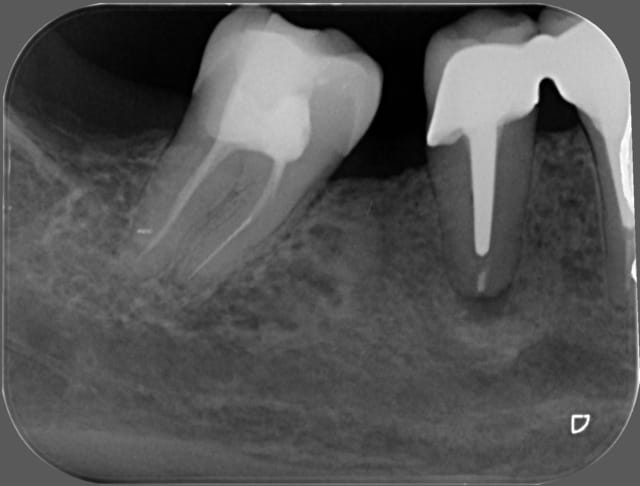

quel serait votre attitude thérapeutique quant aux 45 et 22 ?

en sachant que son opération est prévue le 01/09.

Impossible de donner une réponse définitive sans plus de données, mais rapidement, d'après les radios :

Je laisse 22, le risque est essentiellement mécanique.

Pour 45, si asymptomatique depuis de nombreuses années, je laisse aussi.

Surveillance radiologique bien sûr, et stabilisation occlusale de 23.

patiente diabétique,

aucune symptomatologie bucco-dentaire

sauf que le radiologue qui a fait la pano ( ordo faite par le chir ) note image apicale au niveau de 45 et de 22.